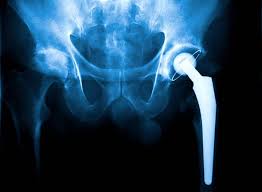

Varunam Super Speciality Hospital in Mandla offers precision hip replacement, providing advanced orthopedic care that emphasizes accuracy, safety, and optimal long-term joint function. The hospital combines experienced orthopedic surgeons, modern surgical technology, and a patient-focused approach to deliver high-quality hip replacement procedures.

Equipped with state-of-the-art operation theatres, digital imaging systems, and specialized rehabilitation facilities, Varunam ensures precise implant positioning and minimal tissue damage. Precision hip replacement allows for improved joint alignment, enhanced stability, and faster recovery. With structured post-operative care and physiotherapy programs, the hospital has become a trusted choice for precision hip replacement in Mandla.